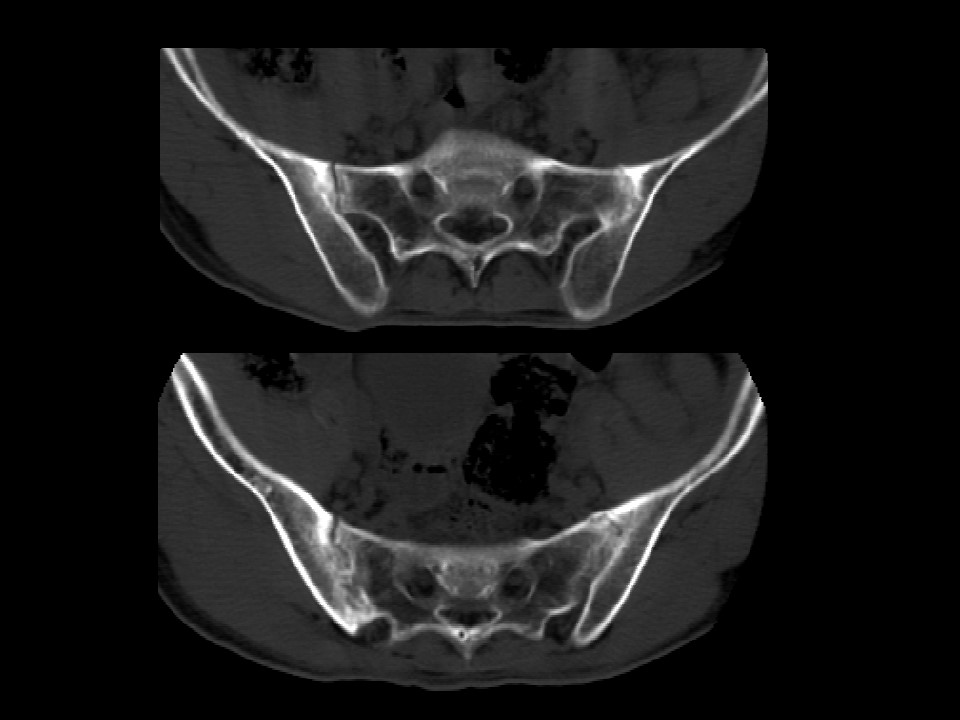

强直性脊柱炎的护理PPT 强直性脊柱炎是以中轴关节慢性炎症为主,原因不明的全身性疾病。其特点为累及骶髂关节常发生椎间盘纤维环及其附近韧带钙化和骨性强直。...